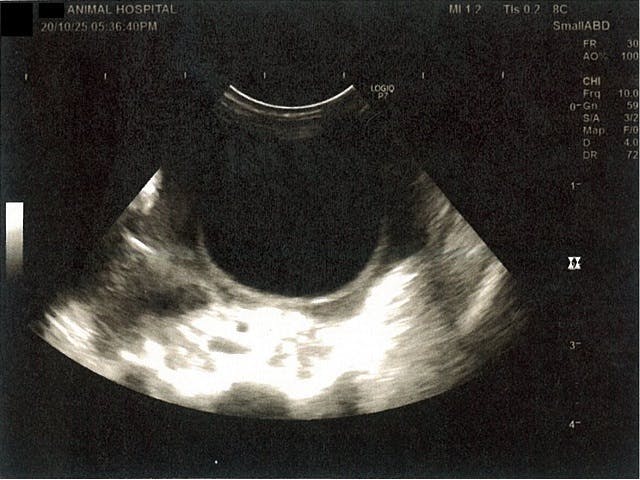

《心臓周りの胸部以外の全ての腹部で腹水がみられるとの診断です》

心臓のみ腹水が確認できないエコー写真